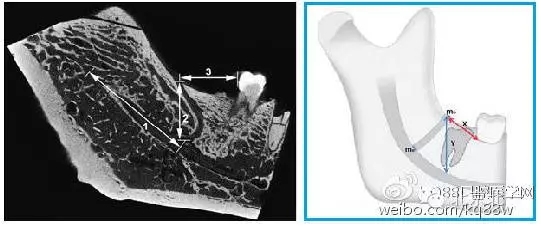

圖四 磨牙后管的線性測量

1.從下頜孔到下頜磨牙后管分支起點(diǎn)的距離;2.下頜磨牙后管的垂直高度(X);3.從下頜后孔到第二或第三磨牙遠(yuǎn)中的水平距離(Y)。